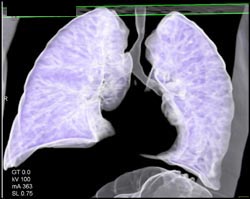

Airway Narrowing Due to Double Arch